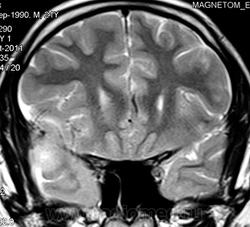

ГМ. Менингосаркома. +

Менингосаркома.